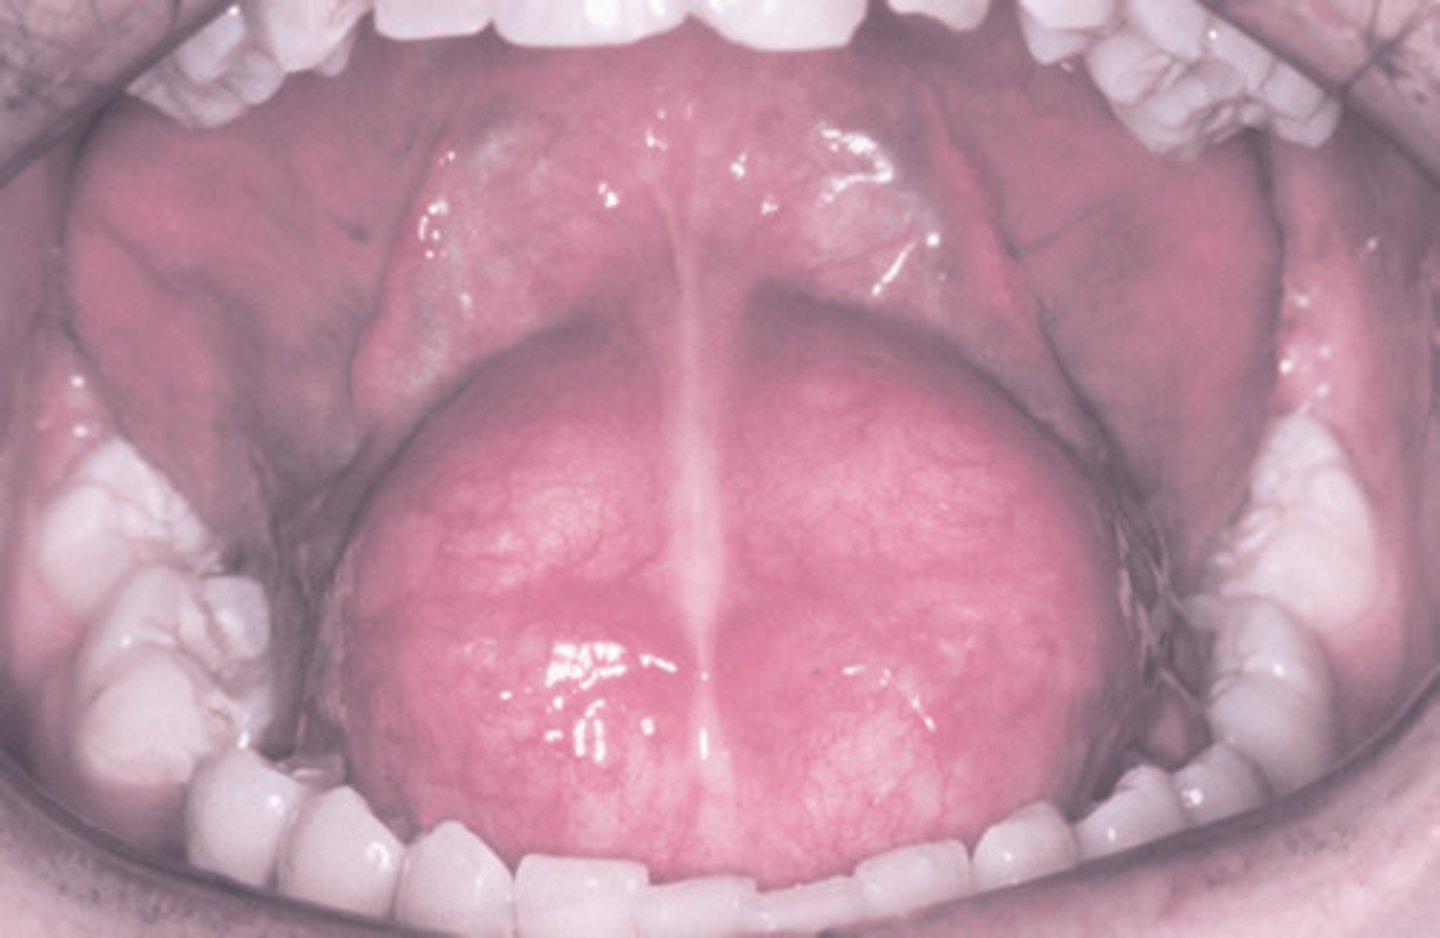

What are the common locations for Oral Lymphoepithelial Cysts?

Intraorally:

1. floor of mouth

2. ventral/posterior tongue

What are intraoral clinical features of Oral Lymphoepithelial Cysts?

well-defined pinkish-yellow raised nodule